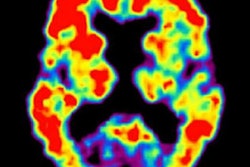

Amyloid-positive (left) and amyloid-negative (right) PET scans can be used to diagnose or rule out Alzheimer's disease in individuals with memory loss or cognitive decline. Images courtesy of UCSF Memory and Aging Center."In this study, amyloid PET results were negative in a significant minority of patients with a pre-PET diagnosis of Alzheimer's disease, and conversely most patients with negative scan results had a pre-PET diagnosis of Alzheimer's disease," the researchers noted. "This diagnosis [of Alzheimer's] and subsequent treatment [for the disease] may have persisted if these patients had no access to amyloid PET."